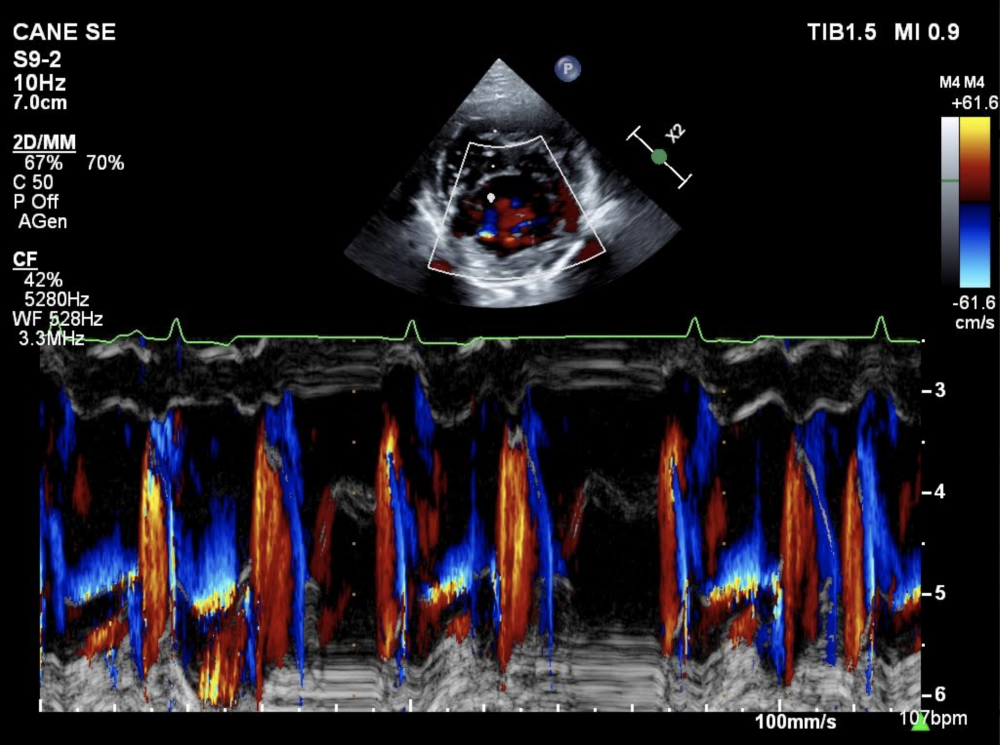

- Esame ecocardiografico – ecoDoppler – strain/strain rate